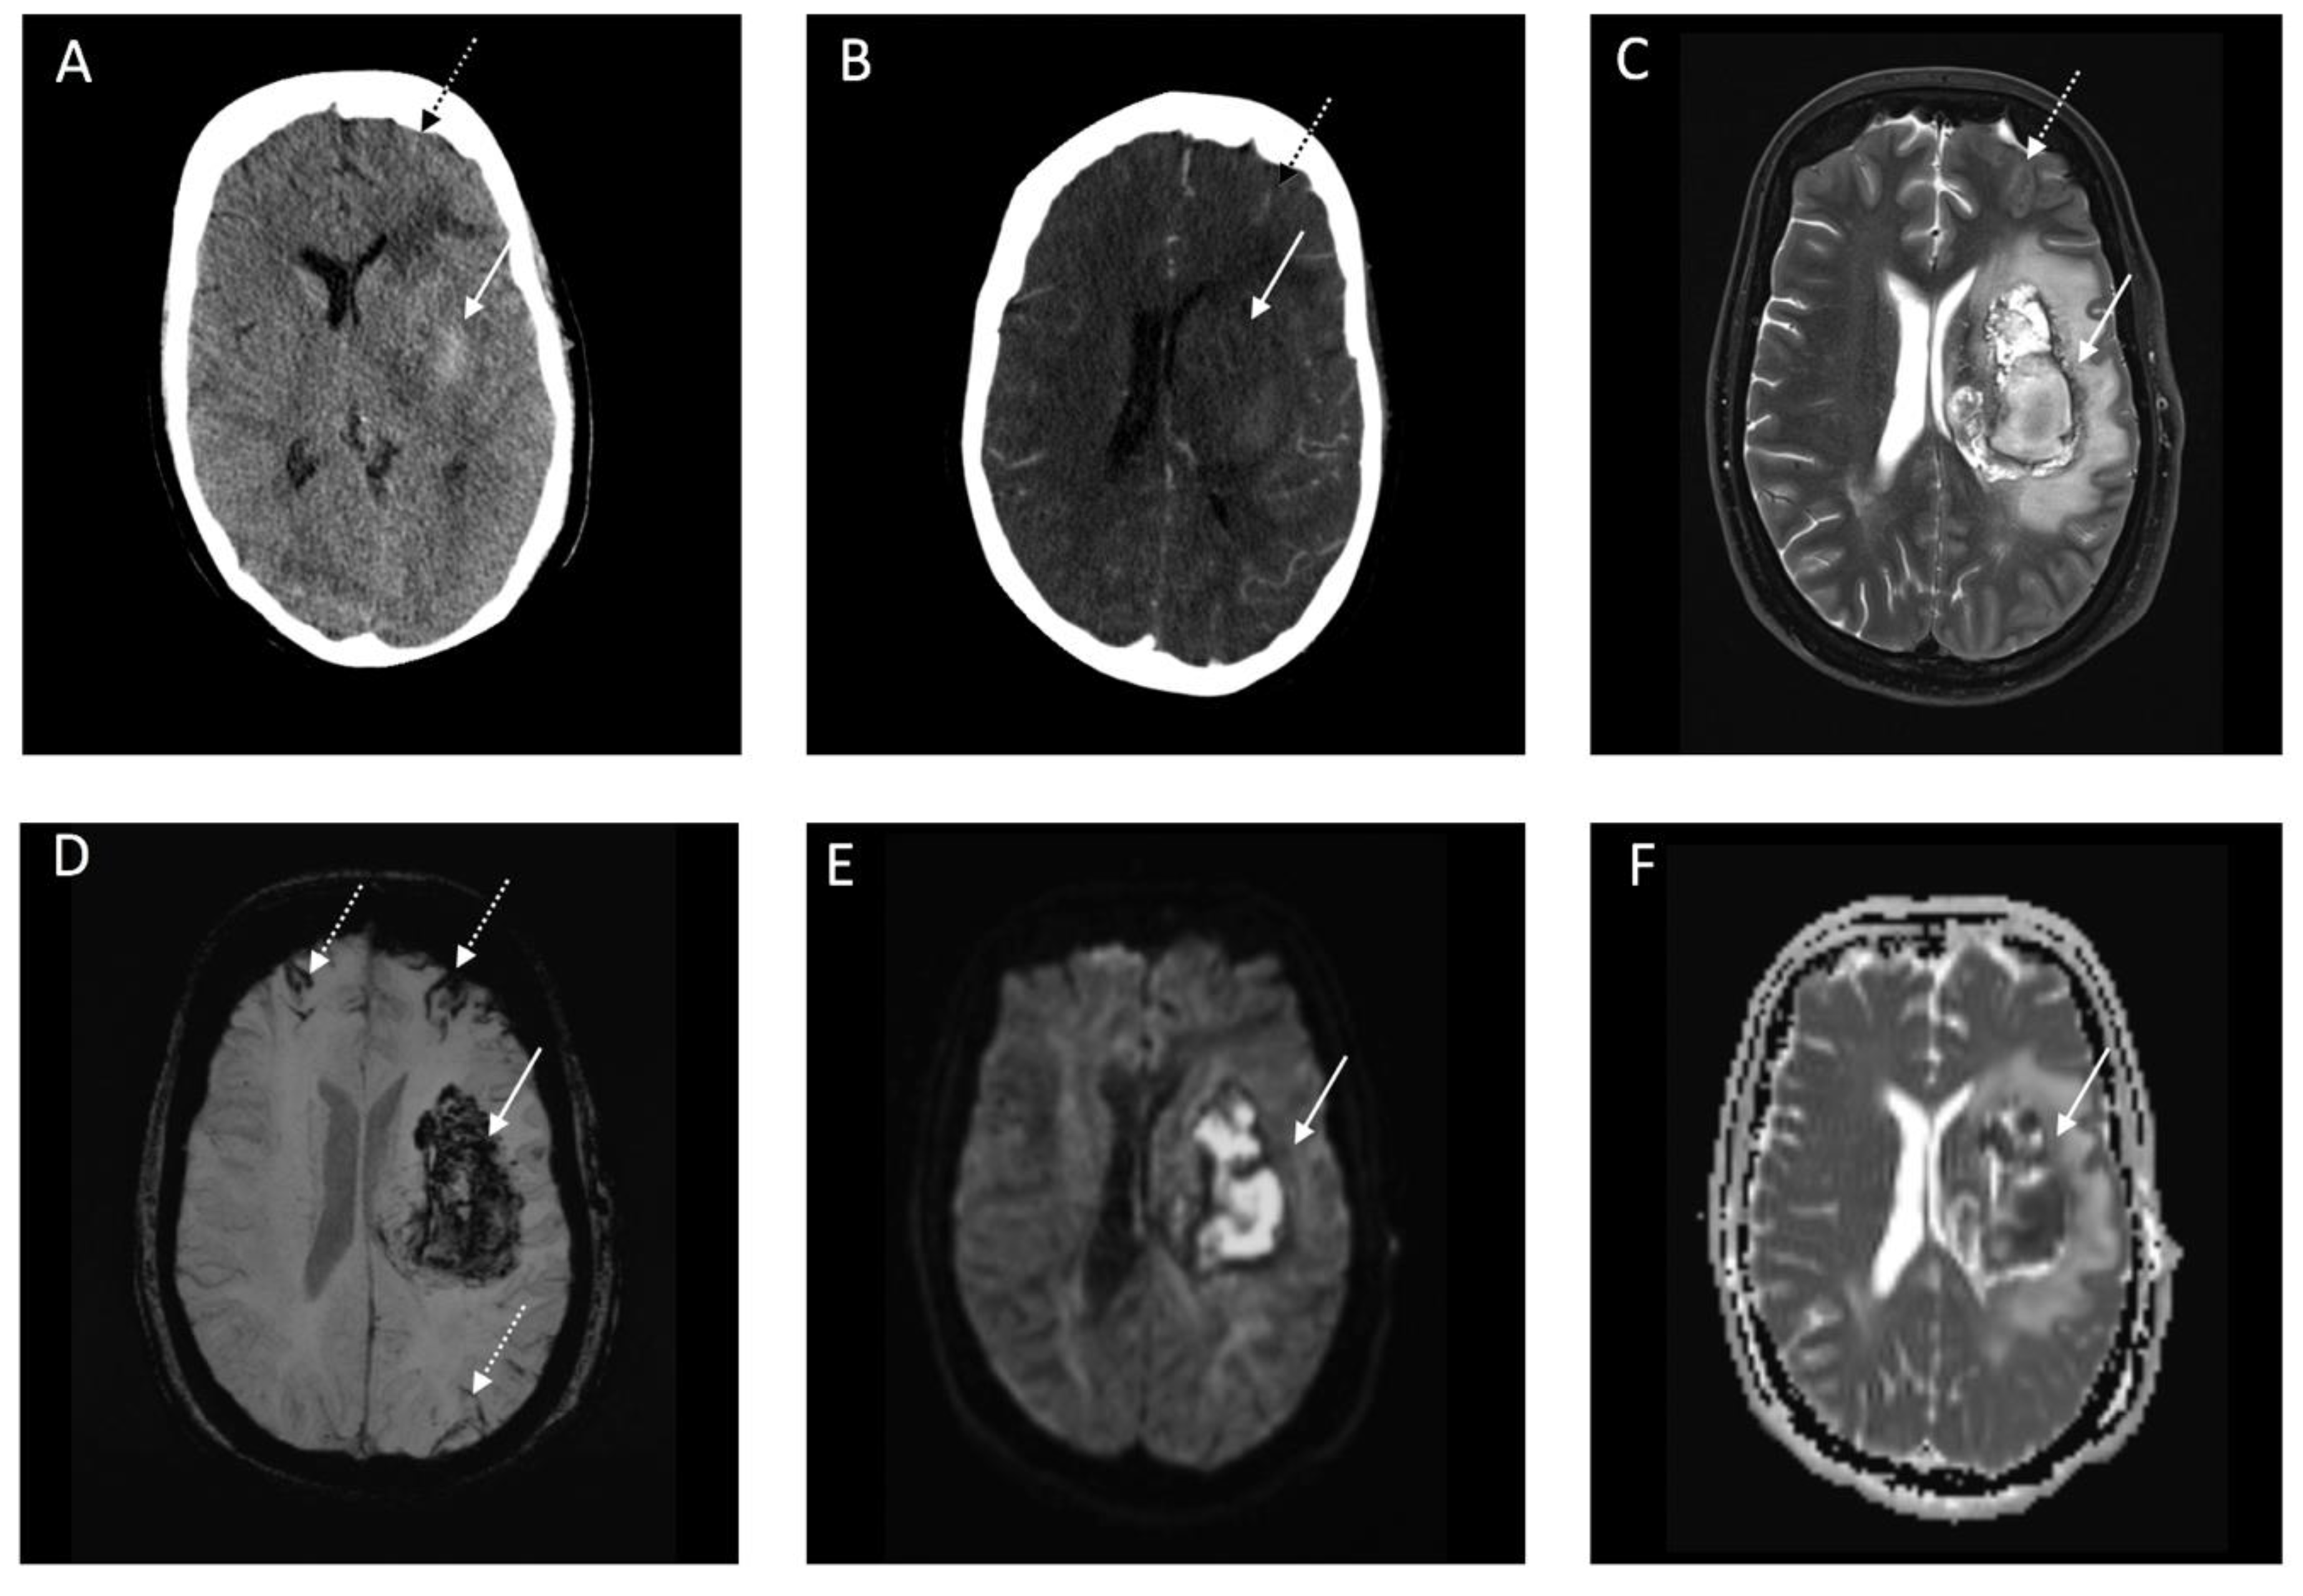

3.2. Imaging and Clinical Findings